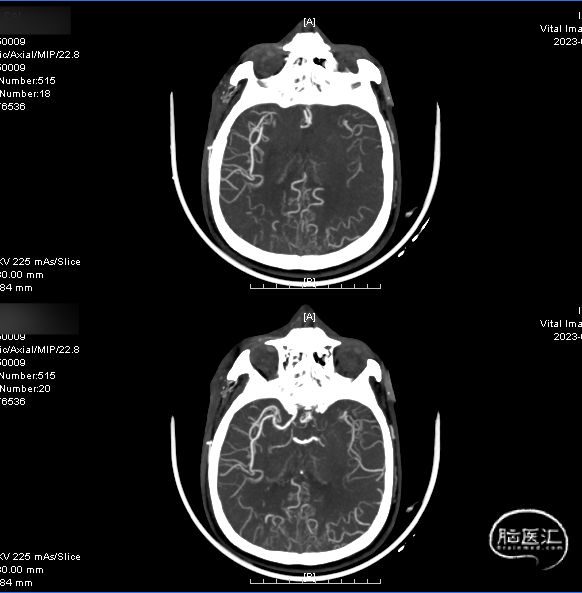

术前CTA:双侧颈内动脉闭塞,代偿可。

术前CTA:颅内代偿可。